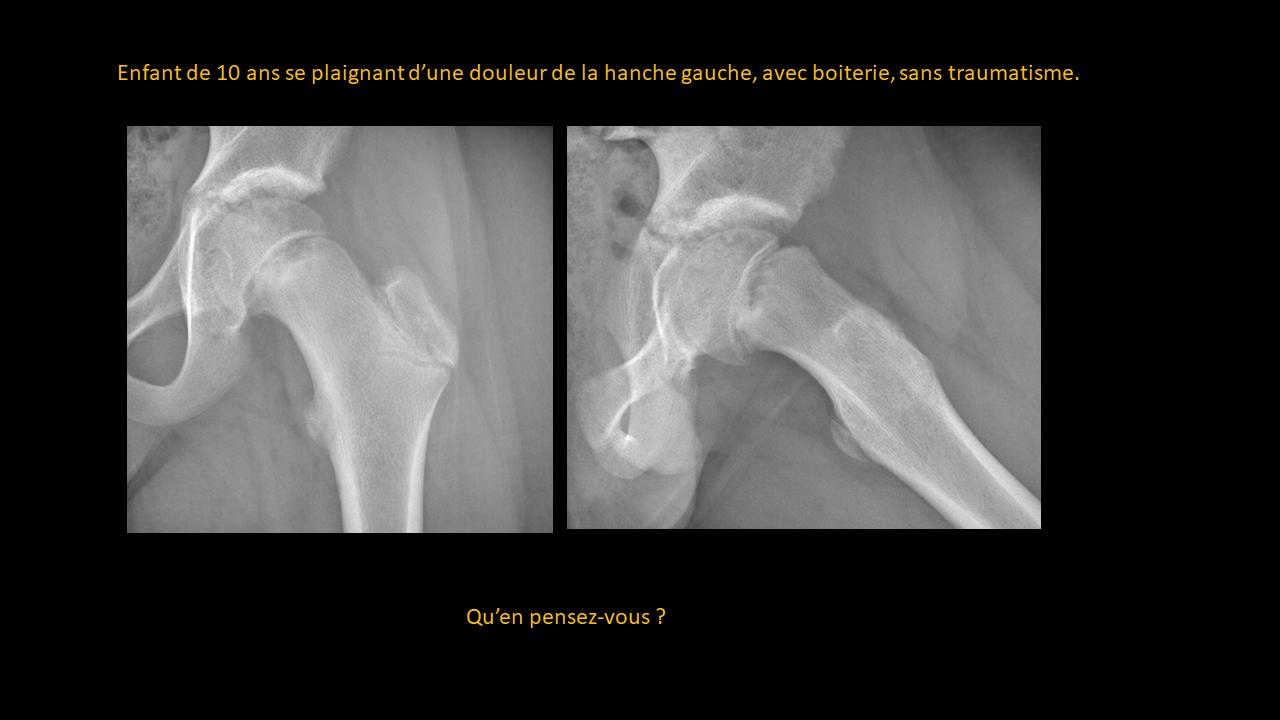

Présentation clinico-radiologique 86

_______ cliquer ici pour la réponse ________